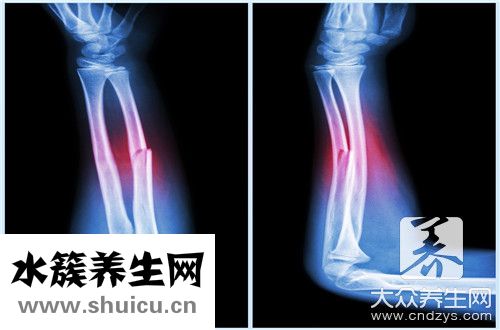

肱骨是人體中上肢最大的骨骼,肱骨上端是構成肩關節的重要部分,肱骨下端是構成肘關節的部位,但肱骨出現骨折的概率也非常高,一般與個人行為有關,老年人群骨骼...